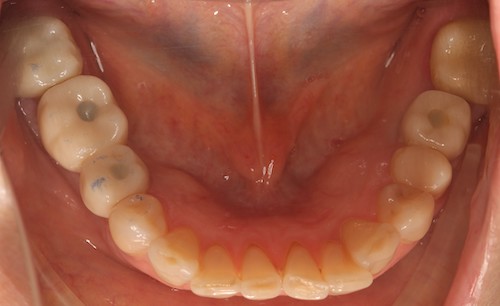

До